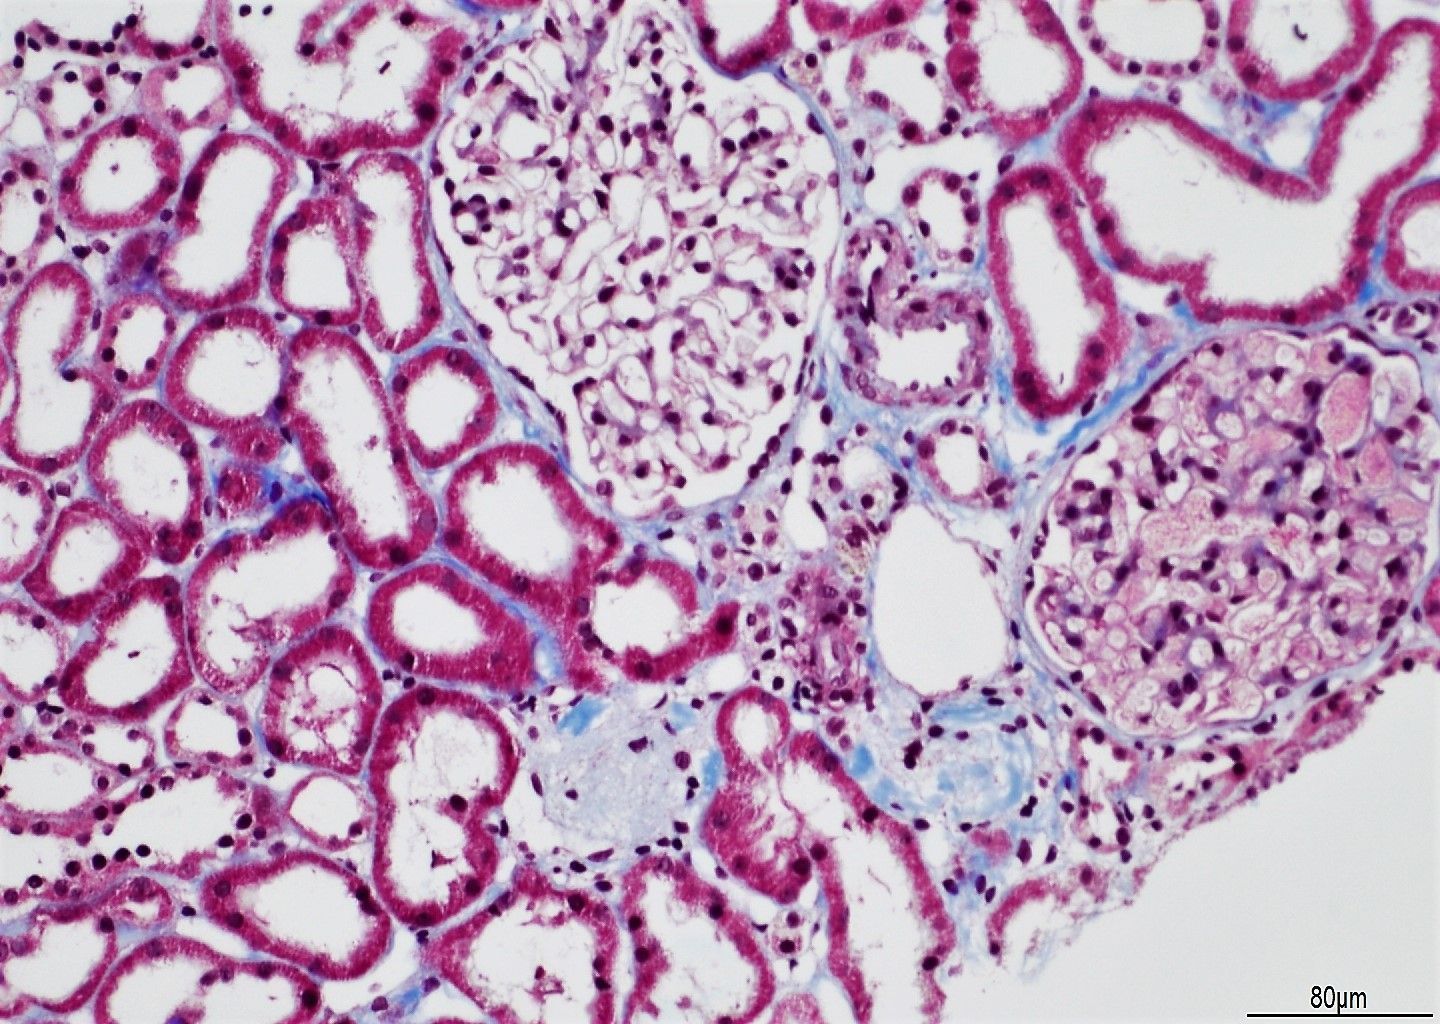

- Online na library ng mga larawang may kulay na nagpapakita ng pinakamainam at sub-optimal na paglamlam